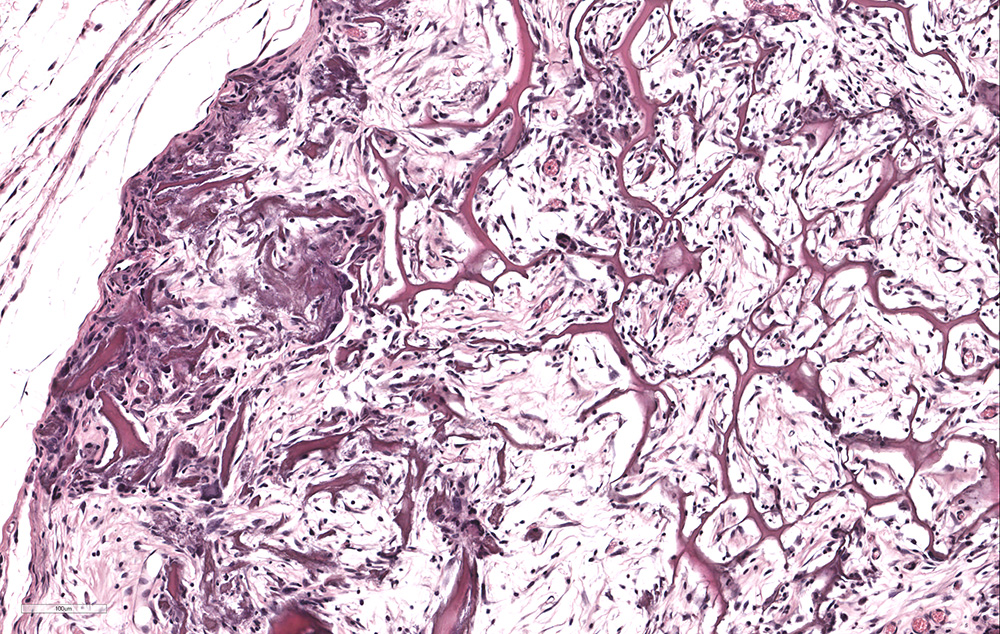

- Valutazioni istologiche, istochimiche ed immunoistochimiche su campioni decalcificati o inclusi in resine (epossidiche ed acriliche)

- Valutazioni istomorfometriche statiche e dinamiche per la valutazione dell’integrazione di biomateriali ai tessuti o della risposta tessutale ad un trattamento terapeutico farmacologico e/o fisico attraverso misure morfometriche o score semiquantitativi